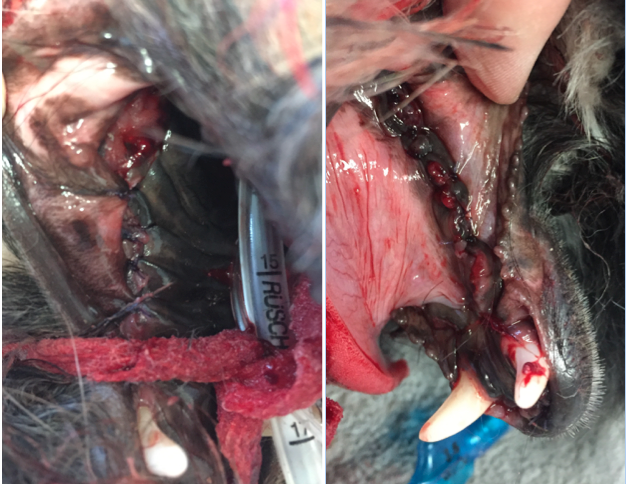

Es ist in so einer Situation auch durchaus möglich, dass der Kiefer intra OP frakturiert sobald der Zahn extrahiert wurde und dann kein Halt mehr besteht. Da jedoch der Zahn auch die Ursache der Entzündung ist, blieb keine andere Wahl, als alle Zähne mit der größtmöglichen Vorsicht zu extrahieren. Glücklicherweise blieb der Kiefer stabil und es musste keine Osteosynthese vorgenommen werden.

Die Wunden wurden alle sorgfältig kürretiert (dabei wurden mit einem scharfen Löffel Gewebereste und Schmutz entfernt), gespült und das Zahnfleisch in Einzelheften vernäht. Das Nahtmaterial hierfür sollte resorbierbar, monofil und mit atraumatischer Nadel sein, damit es das empfindliche Zahnfleisch so wenig wie möglich verletzt.